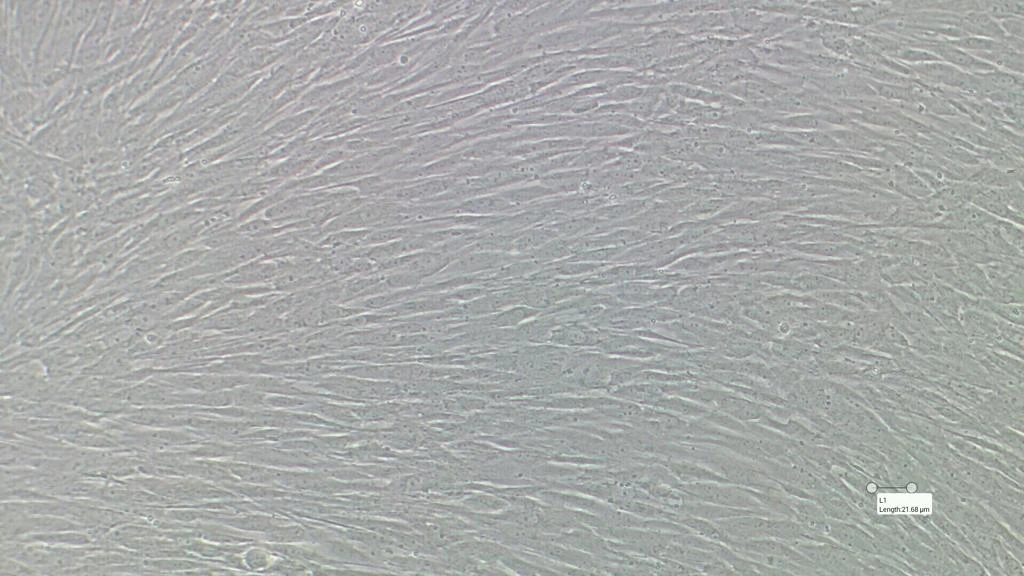

Atualmente, Moira tem um grande desafio em mãos. Ela faz parte da equipe que pesquisa o uso células-tronco para auxiliar no tratamento de casos graves da Covid-19. Moira trabalha com células-tronco mesenquimais, coletadas de dentes saudáveis de doadores jovens. Uma vez isoladas, as células são multiplicadas no Centro de Processamento Celular (CPC), da Curityba Biotech, e são infundidas em pacientes acometidos de síndrome respiratória aguda grave e que estejam internados em Unidade de Terapia Intensiva (UTI).

"As células-tronco mesenquimais são células imaturas que, por ainda não estarem especializadas, são capazes de se multiplicar inúmeras vezes e também secretam muitas substâncias ativas. Algumas das substâncias que as células-tronco mesenquimais produzem têm capacidade imunomoduladora, ou seja, são capazes de reequilibrar essa resposta exagerada do organismo, orquestrando os processos de reparo", detalha.